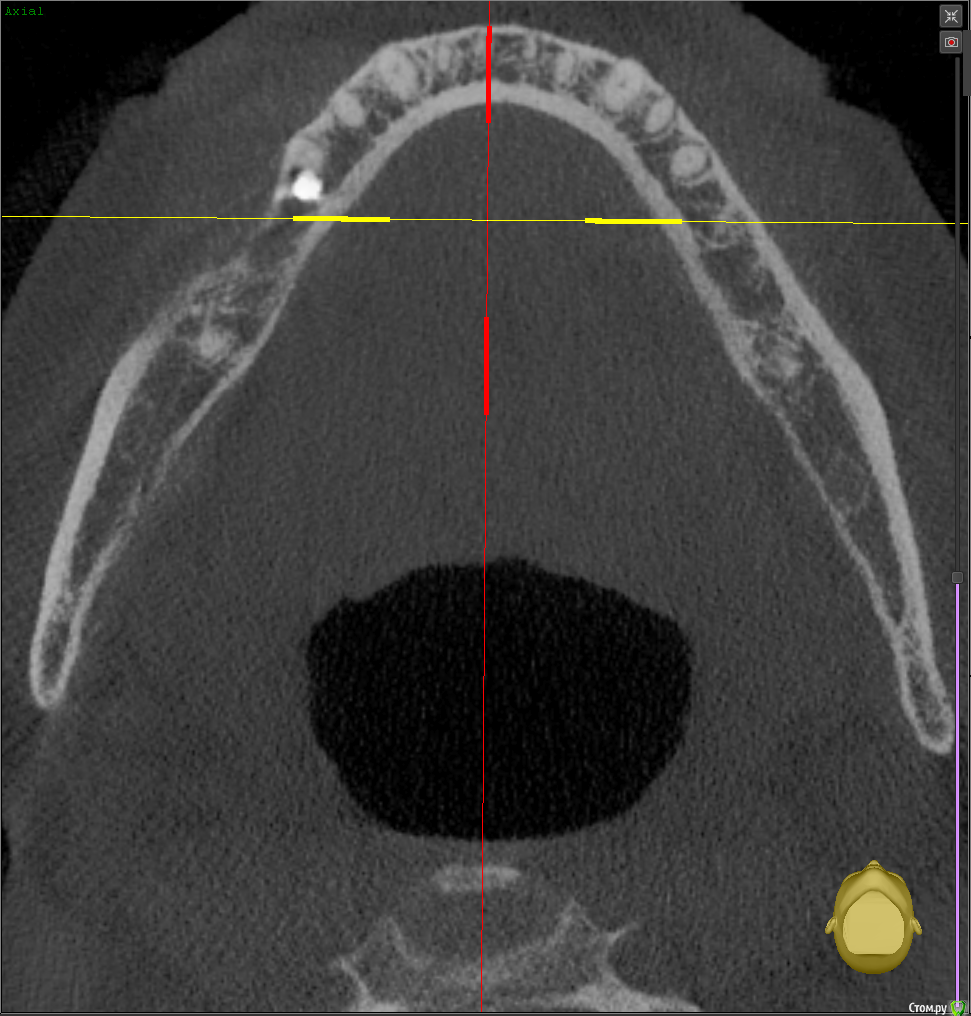

Тата Богачевская Опубликовано 24 октября, 2020 Поделиться Опубликовано 24 октября, 2020 Здравствуйте. Меньше месяца назад на место отсутствующего 46 зуба мне был установлен имплантат с расщеплением альвеолярного гребня. Операция прошла хорошо, никаких осложнений. В настоящий момент ничего не беспокоит. Тем не менее положение имплантата у меня вызывает беспокойство - слишком близко к корню 45 зуба и под углом к нему. Однако доктор уверяет, что положение имплантата нормальное, не идеальное конечно, но не критичное. Скажите, пожалуйста, угрожает ли такое положение имплантата 45 зубу, возможно ли будет в дальнейшем установить коронку в правильное положение? Или нужно удалить имплантат? Благодарю.https://yadi.sk/d/Tzd1aKb84eU3wQ Ссылка на комментарий

Тата Богачевская Опубликовано 25 октября, 2020 Автор Поделиться Опубликовано 25 октября, 2020 1.png2.png3.pngВы сделали то, что попросил red butler? Это и есть срезы? Большое спасибо. Ссылка на комментарий

red_butler Опубликовано 25 октября, 2020 Поделиться Опубликовано 25 октября, 2020 Имплант нужно переставить Ссылка на комментарий

колесников Опубликовано 25 октября, 2020 Поделиться Опубликовано 25 октября, 2020 4 месяцаИмплант 46 нужно убрать. Зуб 47ой дистализировать ортодонтически. Переустановить имплант 46 в правильной ортопедической позиции с десневой пластикой. К окончанию лечения вероятно будут вопросы к импланту 16,положение его платформы не самое оптимальное . 1 Ссылка на комментарий